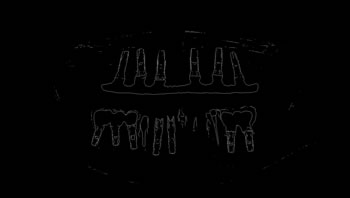

To thoroughly benchmark the methods studied here, the 1,500 images were distributed among 10 categories. The images were named, using whole numbers, in sequential order by category, aiming at not identifying the patients in the study. The process of categorizing the images was performed manually, selecting images individually, counting tooth by tooth, as well as verifying structural characteristics of the teeth. The images were classified according to the variety of structural characteristics of the teeth (see Table 5). Finally, the images were cut out to disregard non-relevant information (white border around the images and part of the spine) generated by the orthopantomograph device. After the clipping process, there was a change in the size of the images to 1991 ×\times 1127 pixels, but without affecting the objects of interest (teeth), as shown in Figure 2. The cropped images were saved on the new dimension to be used in the following stages, which will be presented in the next sections. Figure 3 shows an X-ray image corresponding to each of the categories of our data set.

Refer to caption

Figure 2: Example of the clipping and resizing of the data set images of the present work.